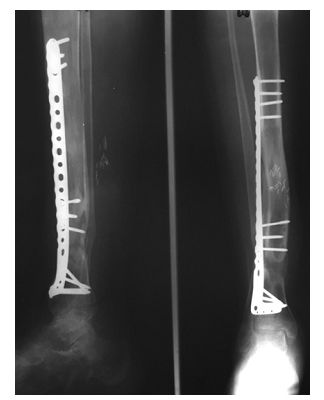

➤ 3、I期术后12个月,搬运到位后,直接上螺钉固定,去除外固定架。

I期术后2年,患者终于获得骨愈合。

◈ 通过这种内外组合,平均愈合时间是266天,14例患者均取得良好的骨愈合。